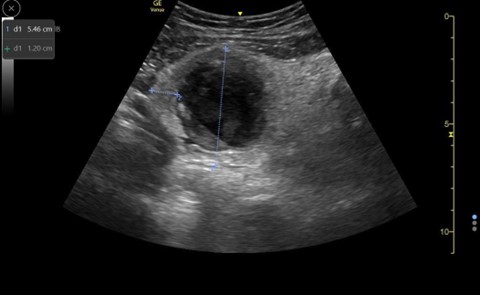

When appendicitis is present, the appendix will measure greater than 6 mm from outer wall to outer wall, with a wall thickness greater than 3 mm and lack compressibility. (Images 1, 8, and 9) (Remember, you may want to do these measurements after you have obtained your images, given your patient a high five and a sticker, and stepped aside to perform measurements on the machine.) An inflamed appendix can demonstrate a “ring of fire” with enhanced color flow. Secondary findings you may see include: an appendicolith, (Image 1), periappendiceal free fluid (Image 10), a target sign (Image 1), enlarged mesenteric lymph nodes, thickening and hyperechogenicity of the overlying peritoneum (Image 8), dilated and hypoactive small bowel, and thickening of the apical cecal pole.

Image 8. Dilated appendix with peri-appendiceal rupture